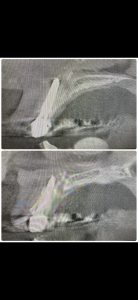

画像からも分かるが、根切断カット長さ、掻爬、殺菌が不十分だったのでは!

これで3回目の治療だそうだ😭

折角のジルコニアは外さずに処置

根管治療4ヶ月くらいで良い結果でますよ

舌側病変も消える!